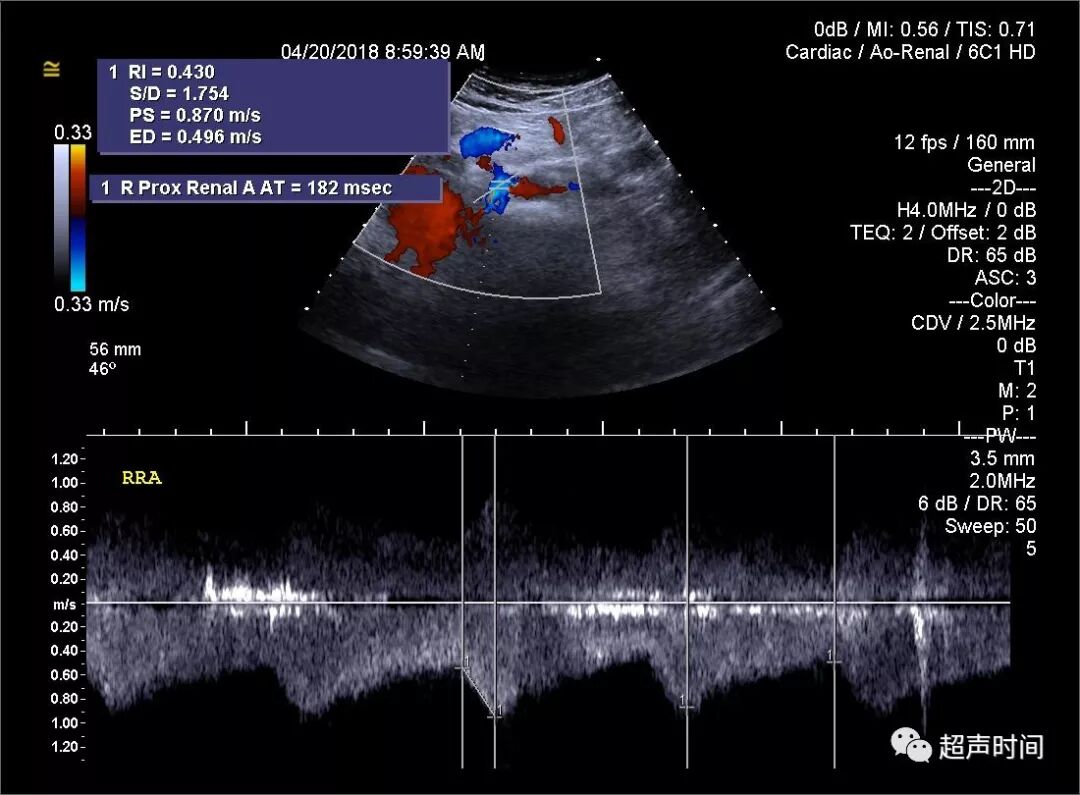

超声检查发现双侧肾主动脉起始段阻力指数(RI)明显减低,且加速时间(AT,正常 ≤ 70 ms)明显延长:右肾动脉流速 87/49 cm/s,RI 0.43,AT 182 ms;左肾动脉流速 93/60 cm/s,RI 0.35,AT 204 ms(图 1)。

图 1 双侧肾主动脉起始段加速时间(AT)明显延长。RRA:右肾动脉;LRA:左肾动脉